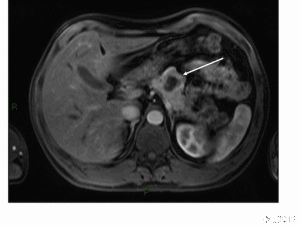

影像學檢查是定位診斷的主要方法,還可同時監測對治療的反應。目前,CT、磁共振成像(MRI)、超聲檢查(US)、內鏡超聲(EUS)等檢查尚未被進一步評價。生長抑素受體顯像的敏感性可根據腫瘤的類型而有所不同,其對於垂體瘤、胃腸胰腺神經性內分泌腫瘤,敏感性超過75%,但對胰島素瘤僅為中度敏感(40%~75%)。

影響治療效果的因素有原發腫瘤灶的位置、腫瘤分期和增殖指數,一般來說,原發胰腺腫瘤、Ⅳ期腫瘤和Ki67陽性提示治療效果欠佳。建議每隔3~6個月,對治療反應進行評價,主要檢測鉻粒素A和特異性激素指標的水平,每6個月行一次CT或MRI檢查。